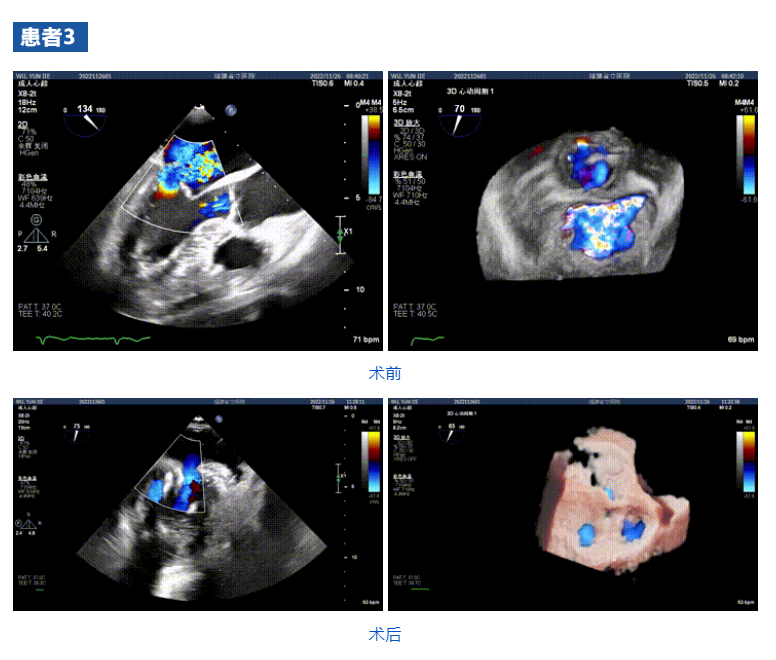

接受治療的三例患者均為器質(zhì)性重度二尖瓣反流(DMR)患者,術(shù)前超聲提示二尖瓣后葉脫垂伴4+反流,左室舒張功能減退。郭延松教授攜同團(tuán)隊(duì)成員陳新敬副教授和洪景宣、方明程、楊清勇主治醫(yī)師、心外科丁杭主任以及超聲科賴(lài)寶春、葉振盛主治醫(yī)師共同進(jìn)行病情討論??紤]到患者高齡、基礎(chǔ)疾病多、STS評(píng)分高,為外科手術(shù)極高危患者,不適合進(jìn)行外科開(kāi)胸二尖瓣手術(shù),因此決定為患者實(shí)施經(jīng)導(dǎo)管緣對(duì)緣修復(fù)介入術(shù)(JensClip經(jīng)導(dǎo)管瓣膜夾系統(tǒng))。

在浙江大學(xué)醫(yī)學(xué)院附屬第二醫(yī)院王建安教授團(tuán)隊(duì)的支持下,手術(shù)經(jīng)股靜脈-房間隔入路,采用全身麻醉插管,在TEE和DSA引導(dǎo)下完成房間隔穿刺。置入JensClip瓣膜夾系統(tǒng)后,在左房調(diào)整瓣膜夾的位置和軸向,后進(jìn)入左室,在TEE引導(dǎo)下捕捉二尖瓣前后瓣葉,并關(guān)閉瓣膜夾。經(jīng)TEE反復(fù)確認(rèn)手術(shù)效果后最終鎖定并釋放瓣膜夾。術(shù)后即刻超聲顯示瓣膜夾位置穩(wěn)定,功能良好,二尖瓣反流由術(shù)前4+減少至微量,手術(shù)圓滿成功。